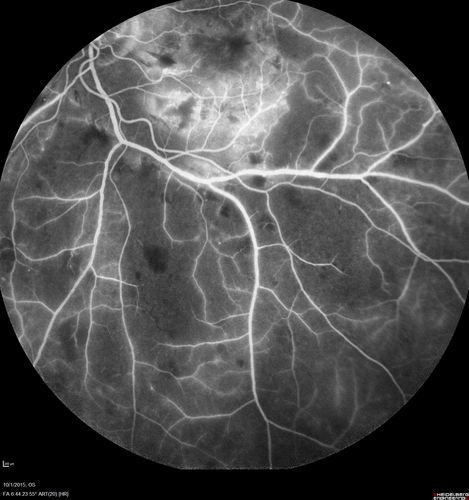

Hairy Cell Leukemia - Retinal Hemorrhage and twig Branch Vein Occlusion

79 year old man He has had hairy cell leukemia since 2002.  He is in remission.  His last blood tests were 9/2018.  He just moved down here and needs a new leukemia doctor.  His vision is fine.

VA OD: Dcc20/25

VA OS: Dcc20/25

IOP: TP: OD:12 OS:12